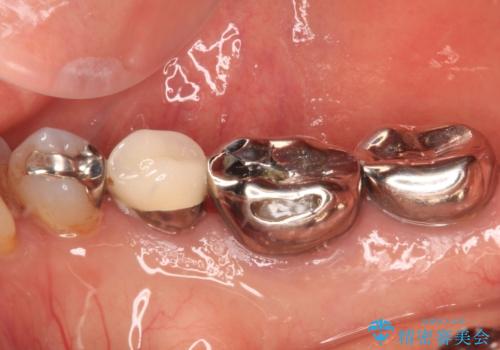

- 奥歯の銀歯に穴が空いてしみるとのことで来院された患者様です。

長年が経過して、徐々に穴が空いてきていたが、最近しみるようになったとのことでした。

痛みの感じ方に異常な所見は認められなかったため、オールセラミッククラウンにて補綴治療を行うこととしました。